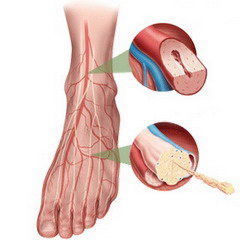

- кожа на стопах становится особенно сухой и может шелушиться;

- в ногах возникает жжение и сильный зуд;

- в ногах возникает боль, усиливающаяся при длительной ходьбе, но частично утихающая во время отдыха.

На более поздних и запущенных стадиях заболевания может возникнуть онемение стоп, выраженная нефропатия или ретинопатия, остеомиелит костей, целлюлит на тыльной стороне стопы, а также появление трофических язв и гангрены пальцев, иногда затрагивающей всю стопу или нижние конечности в целом.

В таких случаях стопы становятся уязвимыми к инфекциям даже при незначительных повреждениях, поэтому крайне важно обращать внимание на ранние признаки проблемы, чтобы избежать серьезных последствий.

Следите за состоянием ног. Ежедневно осматривайте ноги на наличие порезов, трещин или изменений цвета. При первых признаках проблем обращайтесь к врачу для своевременного лечения.